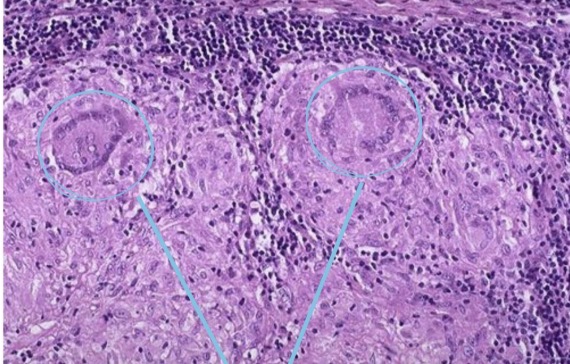

A- identify

B- describe

C- originate from ?

A - squamous cell carcinoma

B- Well differentiated squamous cell carcinoma formed of nests of malignant squamous epithelial cells with keratin pearls

C- from malignant epithelial tissue